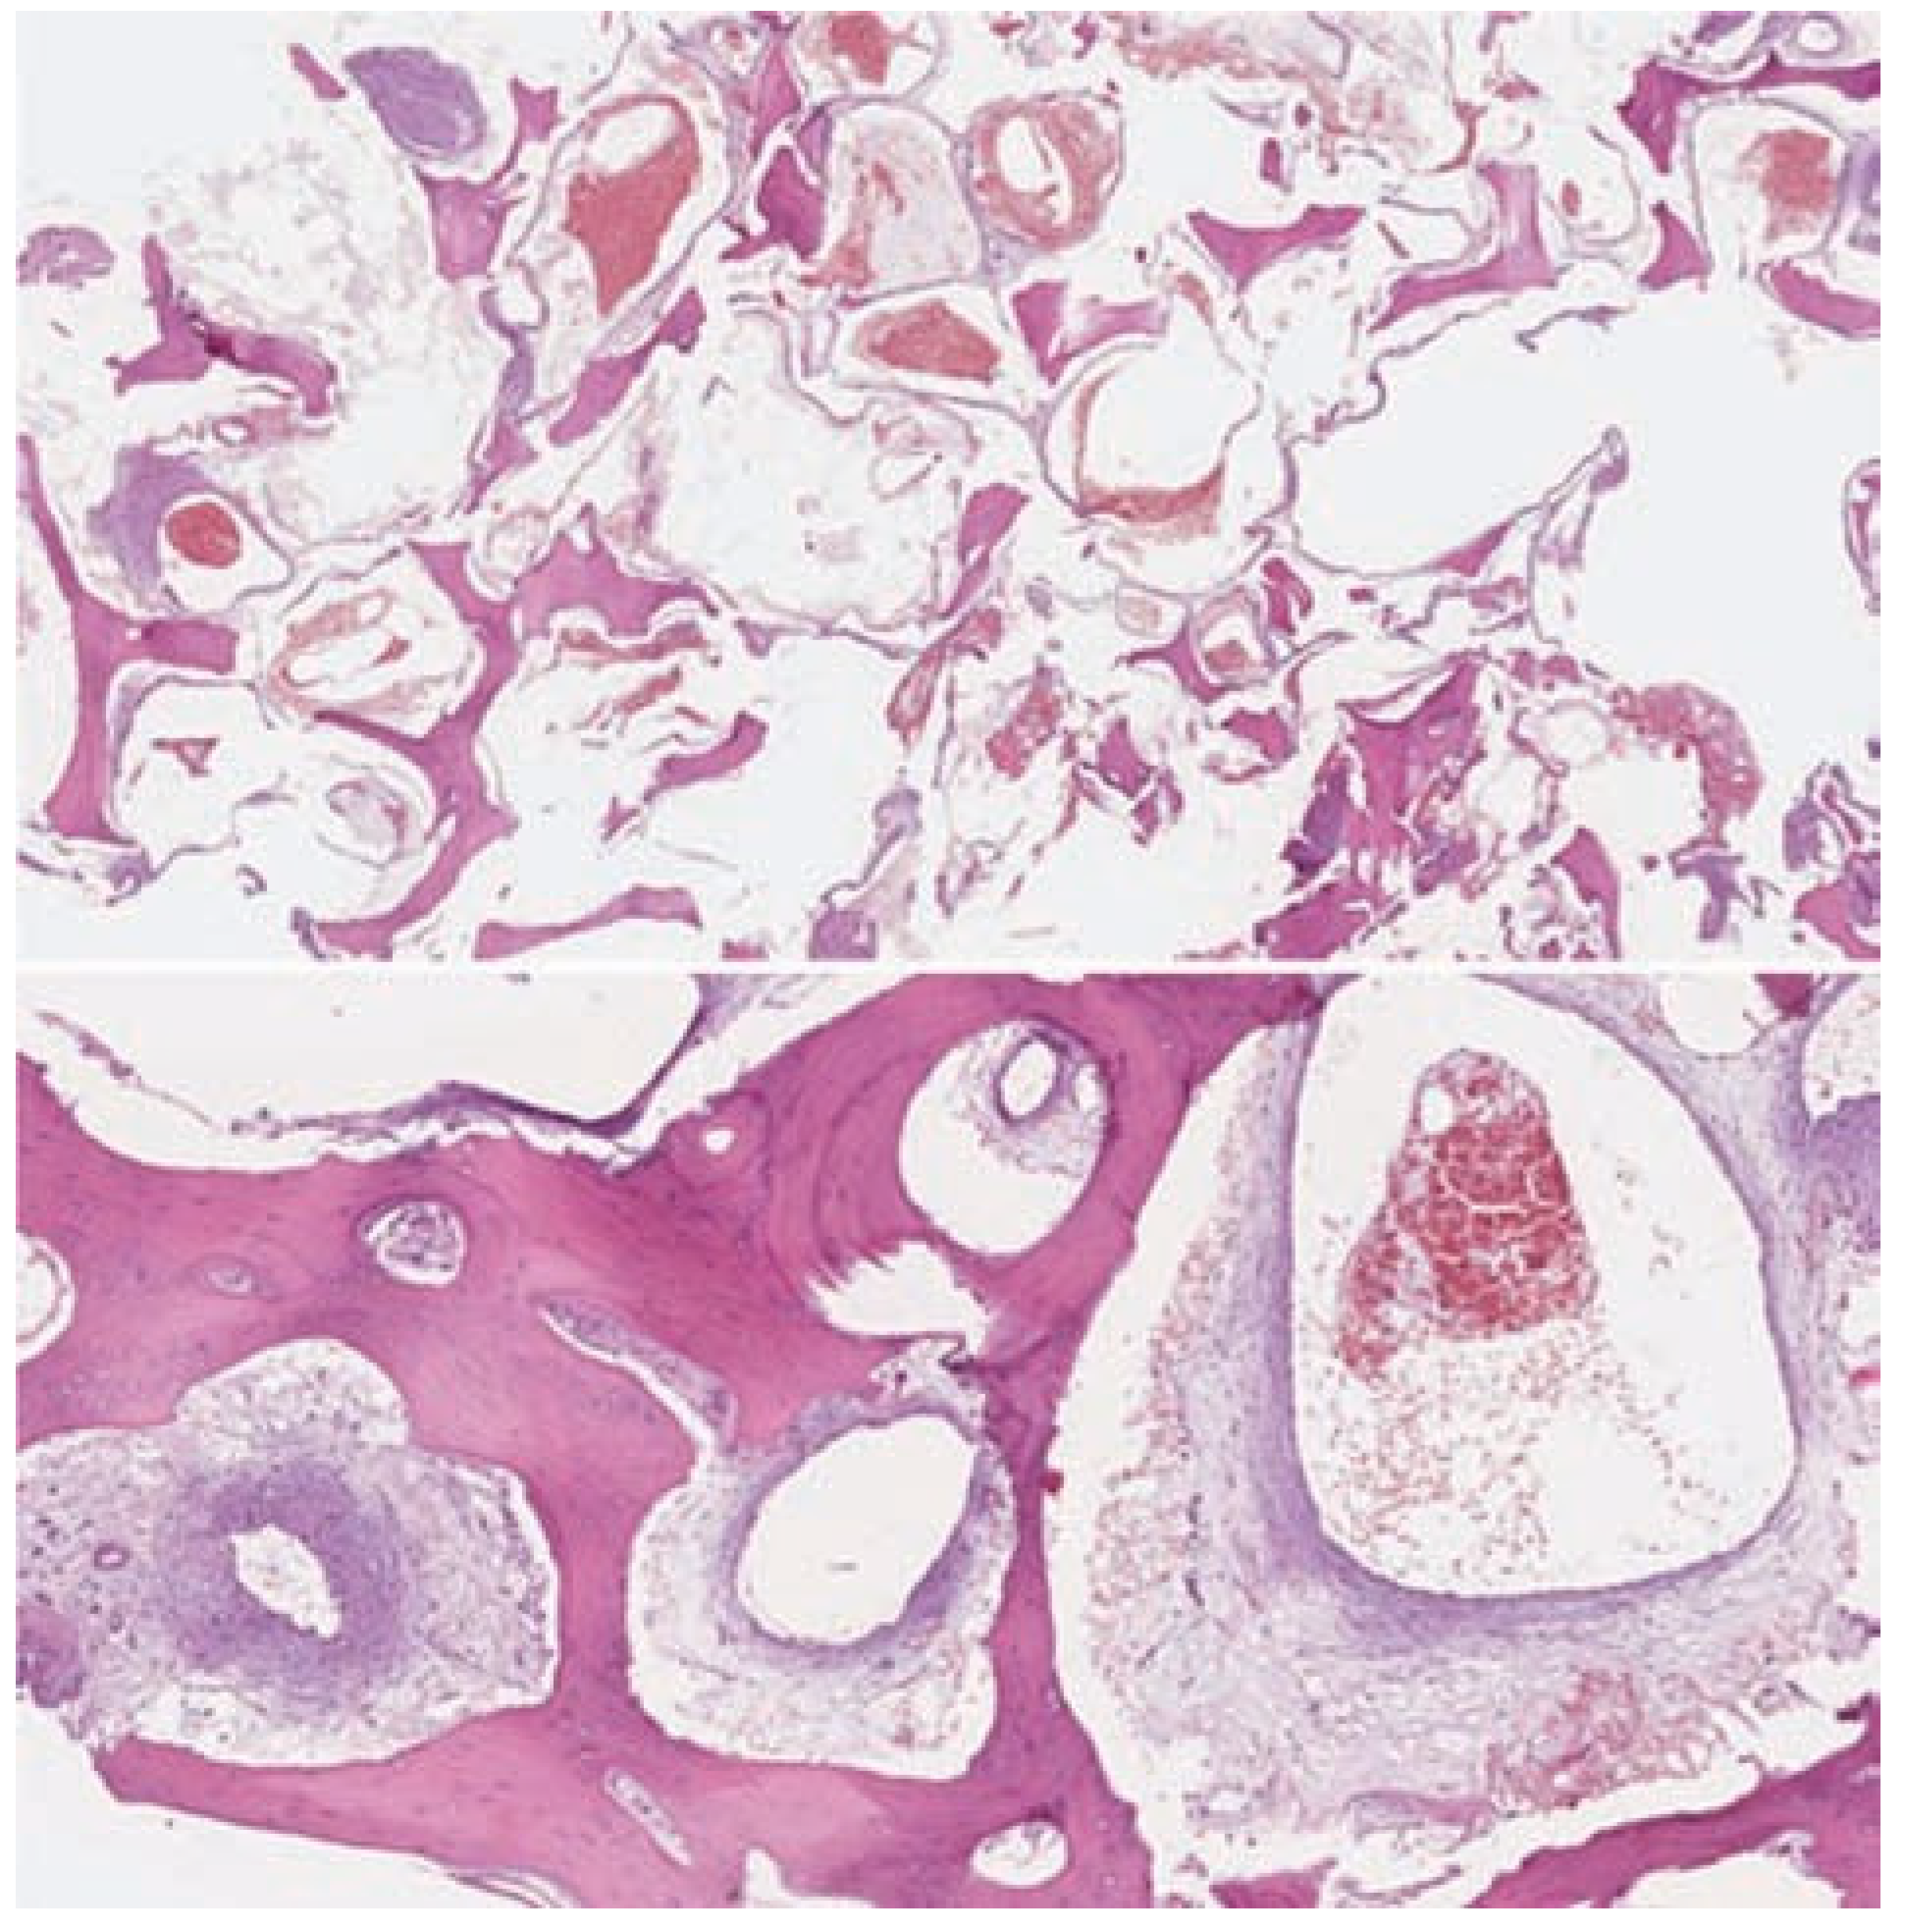

- Moore, S.L.; Chun, J.K.; Mitre, S.A.; Som, P.M. Intraosseous hemangioma of the zygoma: CT and MR findings. AJNR Am J Neuroradiol 2001, 22, 1383–1385. [Google Scholar] [PubMed]

- Kaya, B.; Işılgan, S.E.; Cerkez, C.; Otrakçı, V.; Serel, S. Intraosseous cavernous hemangioma: A rare presentation in maxilla. Eplasty 2014, 14, e35. [Google Scholar] [PubMed]

- Liu, J.K.; Burger, P.C.; Harnsberger, H.R.; Couldwell, W.T. Primary intraosseous skull base cavernous hemangioma. Skull Base 2003, 13, 219–228. [Google Scholar]

- Cheng, N.C.; Lai, D.M.; Hsie, M.H.; Liao, S.L.; Chen, Y.B. Intraosseous hemangiomas of the facial bone. Plast Reconstr Surg 2006, 117, 2366–2372. [Google Scholar]